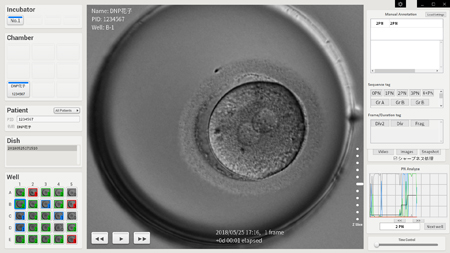

Dai Nippon Printing Co., Ltd. (DNP), Astec Co., Ltd. and Asada Ladies Clinic have jointly developed a next-generation time-lapse incubator system for use in infertility treatment. The new system to be launched by Astec comprises functions including the creation of an optimum culture environment for embryos during infertility treatment, the photographing and recording of the development of those embryos and the automatic detection of insemination via image recognition software.

The partners have successfully developed a next-generation time-lapse incubator system that is more compact than currently available models. It also maintains a culture environment effective in the development of embryos, while photo data-driven deep learning boosts the efficiency of observation work.

The new system was developed based on needs expressed by the Asada Ladies Clinic vis-à-vis currently available time-lapse incubators. In reply to this request, Astec developed the incubator-proper and DNP the software for automatically recognizing the pronucleus of the embryo, after the sperm enters the ovum, but before the genetic material of the sperm and egg fuse.

Software for Recognizing the Pronucleus

Embryologists confirm the pronucleus in order to determine whether each of the multiple embryos from the subject has been fertilized in a normal manner. This, however, requires skill and time. By using the deep learning technology included in the new software, it is possible to boost the efficiency of the observation task through the automatic recognition of the pronucleus, thereby reducing the burden on the embryologist.